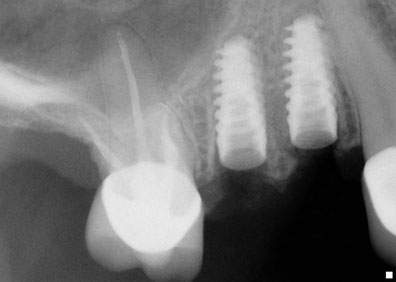

Una solución rápida y segura para hacer posible la instalación de implantes dentales

Fue Philip Boyne, quien en 1960 utilizo por primera vez la técnica Caldwell-Luc, empleada para corregir la falta de espacio maxilo-mandibular elevando la Membrana Sinusal en la zona de molares y premolares, colocando en la base del seno un injerto compuesto por hueso particulado o corticoesponjoso autógeno (que se origina o engendra a sí mismo ) para el relleno de esta cavidad ósea, con la llegada de los implantes de titanio radiculares, se observó que muchas zonas maxilares posteriores, eran inadecuadas en altura y anchura ósea, por lo que se requirió injertar hueso dentro del seno maxilar para hacerlas adecuadas receptoras de implantes. La elevación de senos, es una técnica quirúrgica necesaria cuando no hay suficiente hueso, se añade hueso entre el maxilar superior y los senos maxilares, que son un anexo de las fosas nasales por lo que están en ambos lados de la nariz, la forma y el tamaño de este seno varían en cada persona y con el paso de los años se va haciendo más grande (inadecuado para implantes dentales).

Esta técnica es empleada en cirugía dento-alveolar, oncología y traumatología, con el objeto de  dar arreglo a  un defecto óseo craneofacial etc. La elevación de seno es una solución segura a través de la cual es posible la instalación  de los implantes dentales osteointegrados, dando como resultado estética y funcionalidad a la dentadura, este procedimiento es también conocido como Sinus Lift.

Hace ya más de 15 años que esta técnica se ha vuelto usual, En Dental Evolution Cancún hemos logrado una óptima calidad de injerto óseo con lo que el periodo de formación ósea se ha reducido considerablemente, la cirugía se realiza bajo anestesia local o sedación y su duración es menor a dos horas.

Esta técnica esta recomendada en aquellos casos donde es imposible colocar implantes dentales con la longitud óptima en la parte posterior del maxilar superior ya que en  esta región se posee generalmente una calidad ósea Tipo III ó IV y por esto es necesario utilizar implantes de una longitud mínima de 10mm y del mayor diámetro posible.